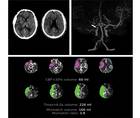

Stroke Snapshot: Intracranial MRI Vessel-Wall Imaging

Mitchell Barnes, DO; Parham Moftakhar, MDMitchell Barnes, DO; Parham Moftakhar, MD